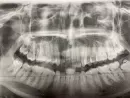

5 дней назад мне удаляли зуб мудрости. Сама десна заживает хорошо, но начал болеть зуб с этой же стороны, но верхний. 6 лет назад в нем удалили нерв, запломбировали канал. Периодически он меня продолжал беспокоить, но я повторно делала снимок и стоматолог ничего в нем не находил. Потом он не беспокоил и я забыла о нем. И вот после удаления зуба он почему то начал болеть, немного отдаёт в голову и нос, боль тянущая, чувствую при смыкании челюсти. На фото, он верхний 3 слева, а удаляли нижний левый крайний.

Да, описанные симптомы могут быть связаны с удалением 36 зуба. Но, всё же рекомендуем вам обратиться к стоматологу - терапевту для оценки состояния 26 зуба и качества лечения каналов.